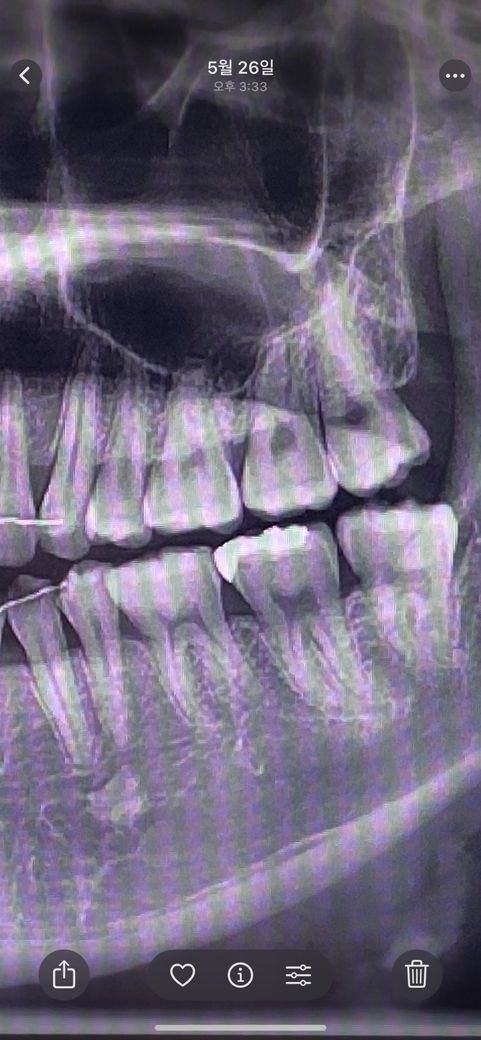

금인레이 엑스레이 2차충치인지 알고싶습니다..

금인레이 한지 6년됐습니다..엑스레이를 찍었는데 금인레이 밑에 작은 검은구멍이 있더라구요 혹시 충치일까 궁금해서 여쭤봅니다. 치과치료할때 아무말없긴했습니다!

엑스레이 상으로는 크게 문제가 잇어 보이진 않습니다. 씹는면은 교모가 되면서 구멍이 생겻을 수도 있습니다.

사진으로 봤을 경우에는 큰 충치가 보이진 않습니다. 금 인레이를 한 치아 주변에 검은색 보인다면 착색이 되었을 가능성이 있습니다. 초기 충치의 경우에는 엑스레이에 보이지 않는 경우도 있으니 이런 경우에는 추가적인 치료가 필요할 수 있습니다.

사진상에 나타나는 검은것이 모두 충치는 아니며 접착제나 시멘트 등이 그렇게 보일 수도 있습니다.